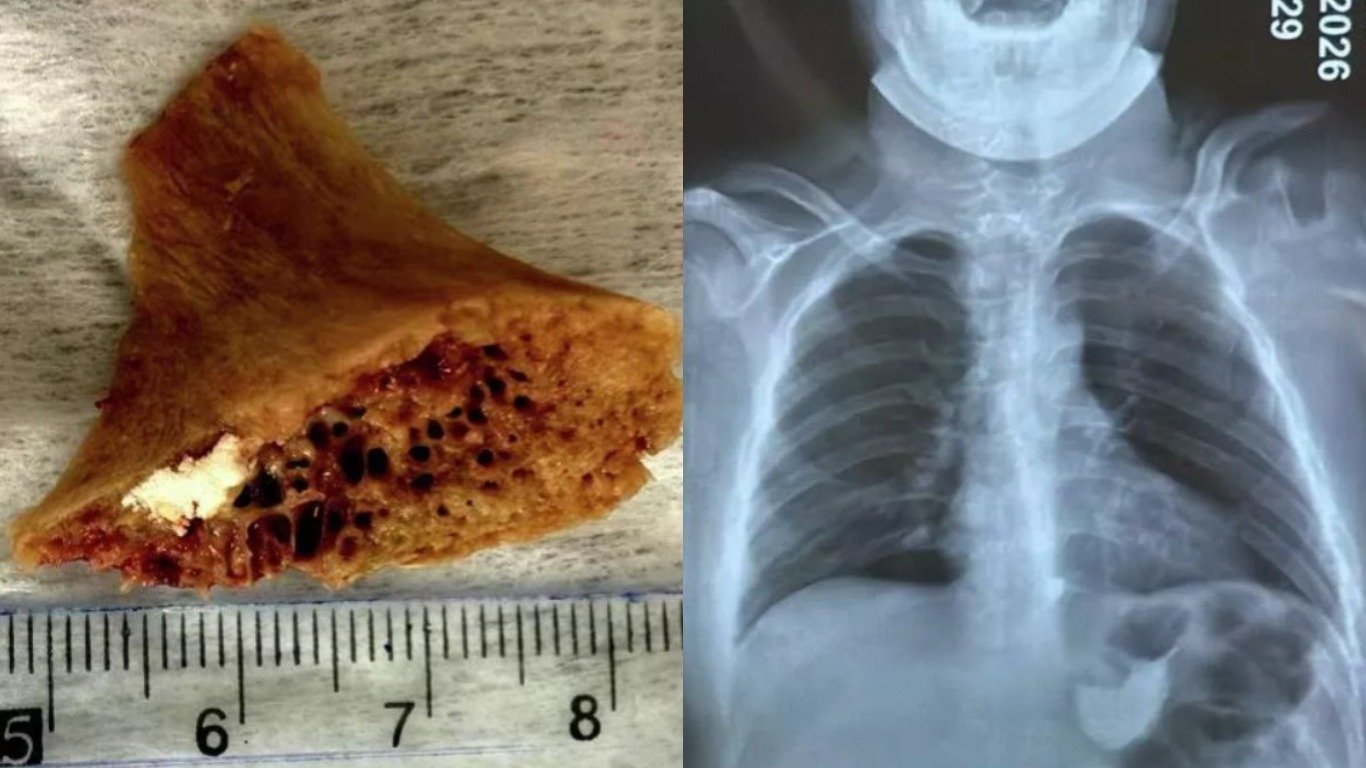

Бишкек шаарында 15 жаштагы өспүрүм сөөк жутуп алып, ал анын кызыл өңгөчүнө тыгылып калган. 3,5×4 см өлчөмүндөгү сөөктү дарыгерлер хирургиялык жол менен чыгарышты. Бул тууралуу Бишкек шаардык медициналык тез жардам балдар клиникалык ооруканасы билдирди.

Маалыматка ылайык, буга чейин өспүрүм шаардагы эки ооруканага кайрылган, бирок ал жерлерде сөөктү чыгаруу мүмкүн болгон эмес. Андан соң бейтап Бишкек шаардык медициналык тез жардам балдар клиникалык ооруканасына жеткирилген.

Аталган мекеменин хирургия бөлүмүнүн дарыгерлери тарабынан операция жасалып, тыгылып калган сөөк алынган. Операция адистердин жана профессорлордун катышуусунда жүргүзүлгөн. Учурда өспүрүмдүн абалы туруктуу, ден соолугу калыбына келүүдө.